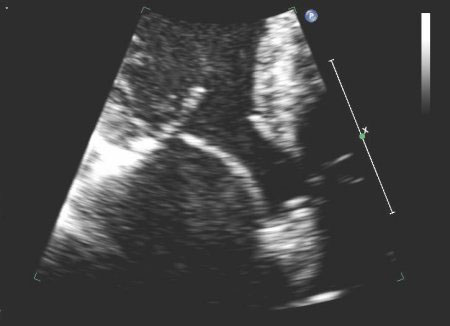

Corte apical de 4 câmaras de folheto mitral posterior instável

Do acervo de Samir Kapadia e Mehdi H. Shishehbor

Veja esta imagem em contexto nas seguintes seções:

Regurgitação mitral